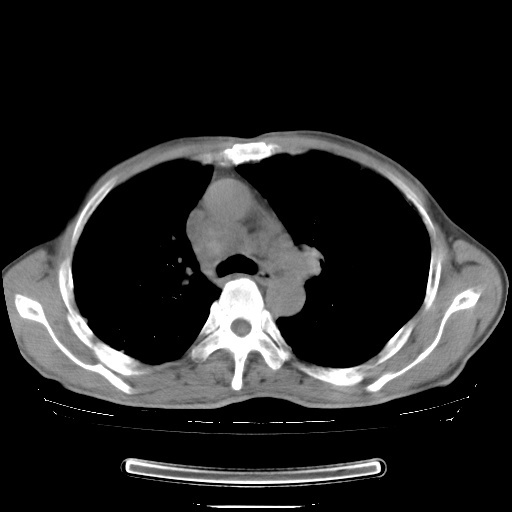

男性患者,63岁。右侧胸背部疼痛2月,加重一周。

考虑:右肺中央型肺癌并右肺下叶不张;两肺尖继发性肺结核。

还有纵隔多处肿大淋巴结及肋骨的改变、两肺多发结节灶。

右下中央型肺癌伴肺内纵膈转移。

右下肺中心型肺癌并肺不张

纵隔淋巴结转移

考虑右中心型肺癌并右下肺不张,肺及纵隔,左肋骨转移。

右肺下叶支气管狭窄闭塞,右下肺不张,气管前间隙淋巴结肿大,两上肺散在分部粟粒灶,沿肺血管支气管束分部,血管支气管束走形较为光滑。考虑右肺中心型肺癌合并肺不张,纵隔淋巴结转移,两上肺癌性淋巴管炎

右肺下叶中心性肺癌并纵隔淋巴结转移,左侧肋骨转移。双肺上叶继发性结核表现。

1)右肺下叶中心性肺癌并纵隔淋巴结转移,两肺转移,左侧肋骨转移。2)双肺上叶继发性结核。

右肺下叶中心性肺癌并纵隔淋巴结及两肺、左侧肋骨转移。双肺上叶继发性结核表现。